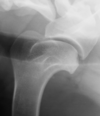

What does this radiograph show?

shoulder osteochondrosis

shoulder osteochondrosis with pieces that floated and remineralized

shoulder OCD (faint flap)